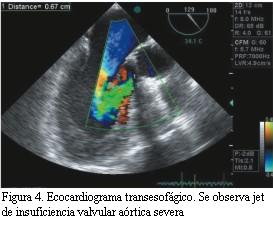

El ecocardiograma transtorácico (ETT) (figuras 1 y 2) muestra aumento de los gradientes transvalvulares con insuficiencia protésica. Se solicita ecocardiograma transesofágico (ETE) que confirma lo observado previamente (figuras 3 y 4): aumento de los gradientes transvalvulares, insuficiencia valvular protésica central severa e hipomovilidad de uno de los discos, compatible con trombosis valvular.

Para confirmar el diagnóstico se realiza cinefluoroscopía con intensificador de imagen en sala de hemodinamia, que confirma válvula mecánica bidisco en posición aórtica con movilidad conservada de un solo disco estando el otro en posición de cierre parcial casi total (figuras 5 y 6).